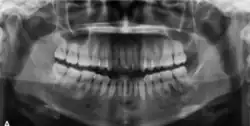

Radiographic features

The radiographic features of central ossifying fibroma can be categorised according to the stages.

In its early stages, central ossifying fibroma (COF) appears as a small, well-defined radiolucent lesion due to its fibrous tissue content. Differential diagnoses at this stage include periapical pathology, central giant cell granuloma, and ameloblastoma.[22][23] As the lesion matures, it exhibits a mixed radiolucent-radiopaque appearance due to progressive calcification.[22] At this stage, it should be differentiated from other mixed jaw lesions such as fibrous dysplasia, calcifying epithelial odontogenic tumour, adenomatoid odontogenic tumour, and condensing osteitis.[22] In its mature form, COF may appear predominantly radiopaque, resembling lesions like odontomas, osteoblastomas, or osteosarcomas radiographically.

COF typically presents with well-defined, smooth, and often corticated borders. As a central lesion, it originates within the medullary bone and expands concentrically in all directions.[24] With growth, it may cause tooth displacement, root resorption, inferior displacement of the mandibular canal, and loss or alteration of the lamina dura of adjacent teeth.[25]

In conclusion, COF most commonly occurs in the mandible and expands from a central epicenter. Radiographically, it presents as a well-defined mixed-density lesion,[26] and Cone Beam CT (CBCT) plays a crucial role in its accurate diagnosis and assessment.

Central Ossifying Fibroma (COF) typically presents as a painless swelling in the posterior mandible, though maxillary involvement can also occur.[31] Larger lesions may lead to facial asymmetry and displacement of adjacent teeth.[32] Radiographically, COF appears as a well-circumscribed, mixed radiolucent–radiopaque lesion with a characteristic sclerotic border, and the degree of radiopacity reflects the stage of mineralization.[33] Cone-beam computed tomography (CBCT) offers detailed evaluation of cortical expansion, root displacement, and internal architecture.[34]